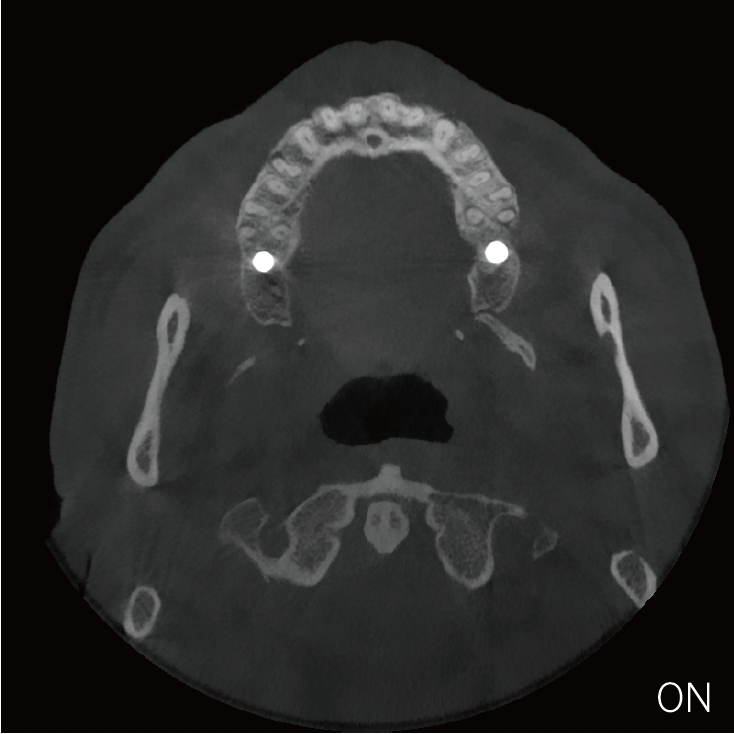

超能去伪 至臻影像

临床样片